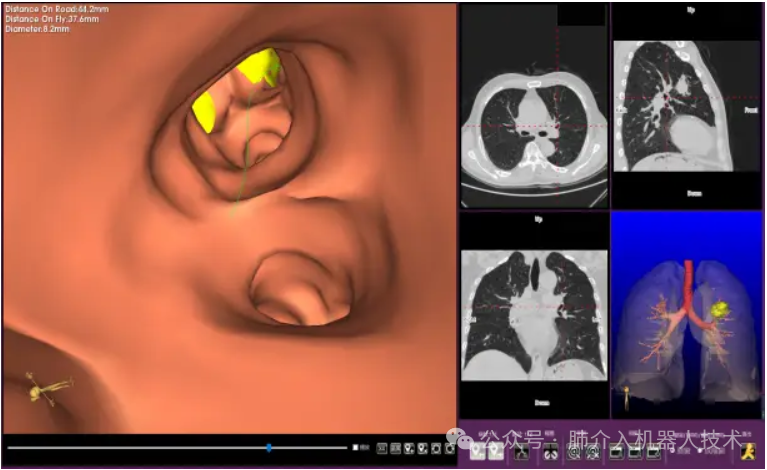

03、奧泰康助力肺部穿刺手術(shù)導(dǎo)航系統(tǒng)獲證

2024年1月31日,經(jīng)國(guó)家藥品監(jiān)督管理局公示,蘇州朗開(kāi)醫(yī)療技術(shù)有限公司自主研發(fā)的肺部穿刺手術(shù)導(dǎo)航系統(tǒng)(國(guó)械注準(zhǔn)20243010222)獲得NMPA批準(zhǔn)上市,奧泰康助力本項(xiàng)目注冊(cè)申報(bào)服務(wù),系2024年奧泰康助力獲得的首張三類(lèi)醫(yī)療器械注冊(cè)證。